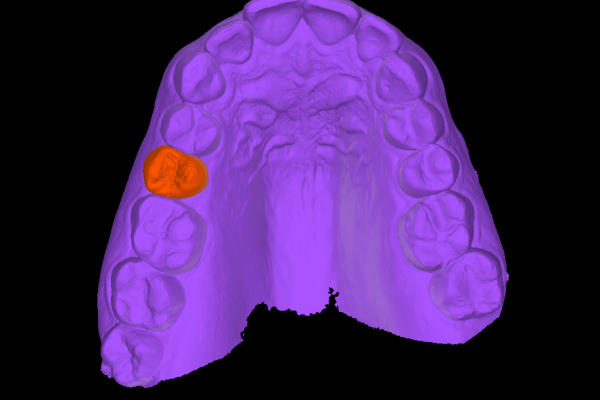

Ubicación precisa del implante

Colocar implantes completamente rodeados de hueso asegura su durabilidad y estabilidad